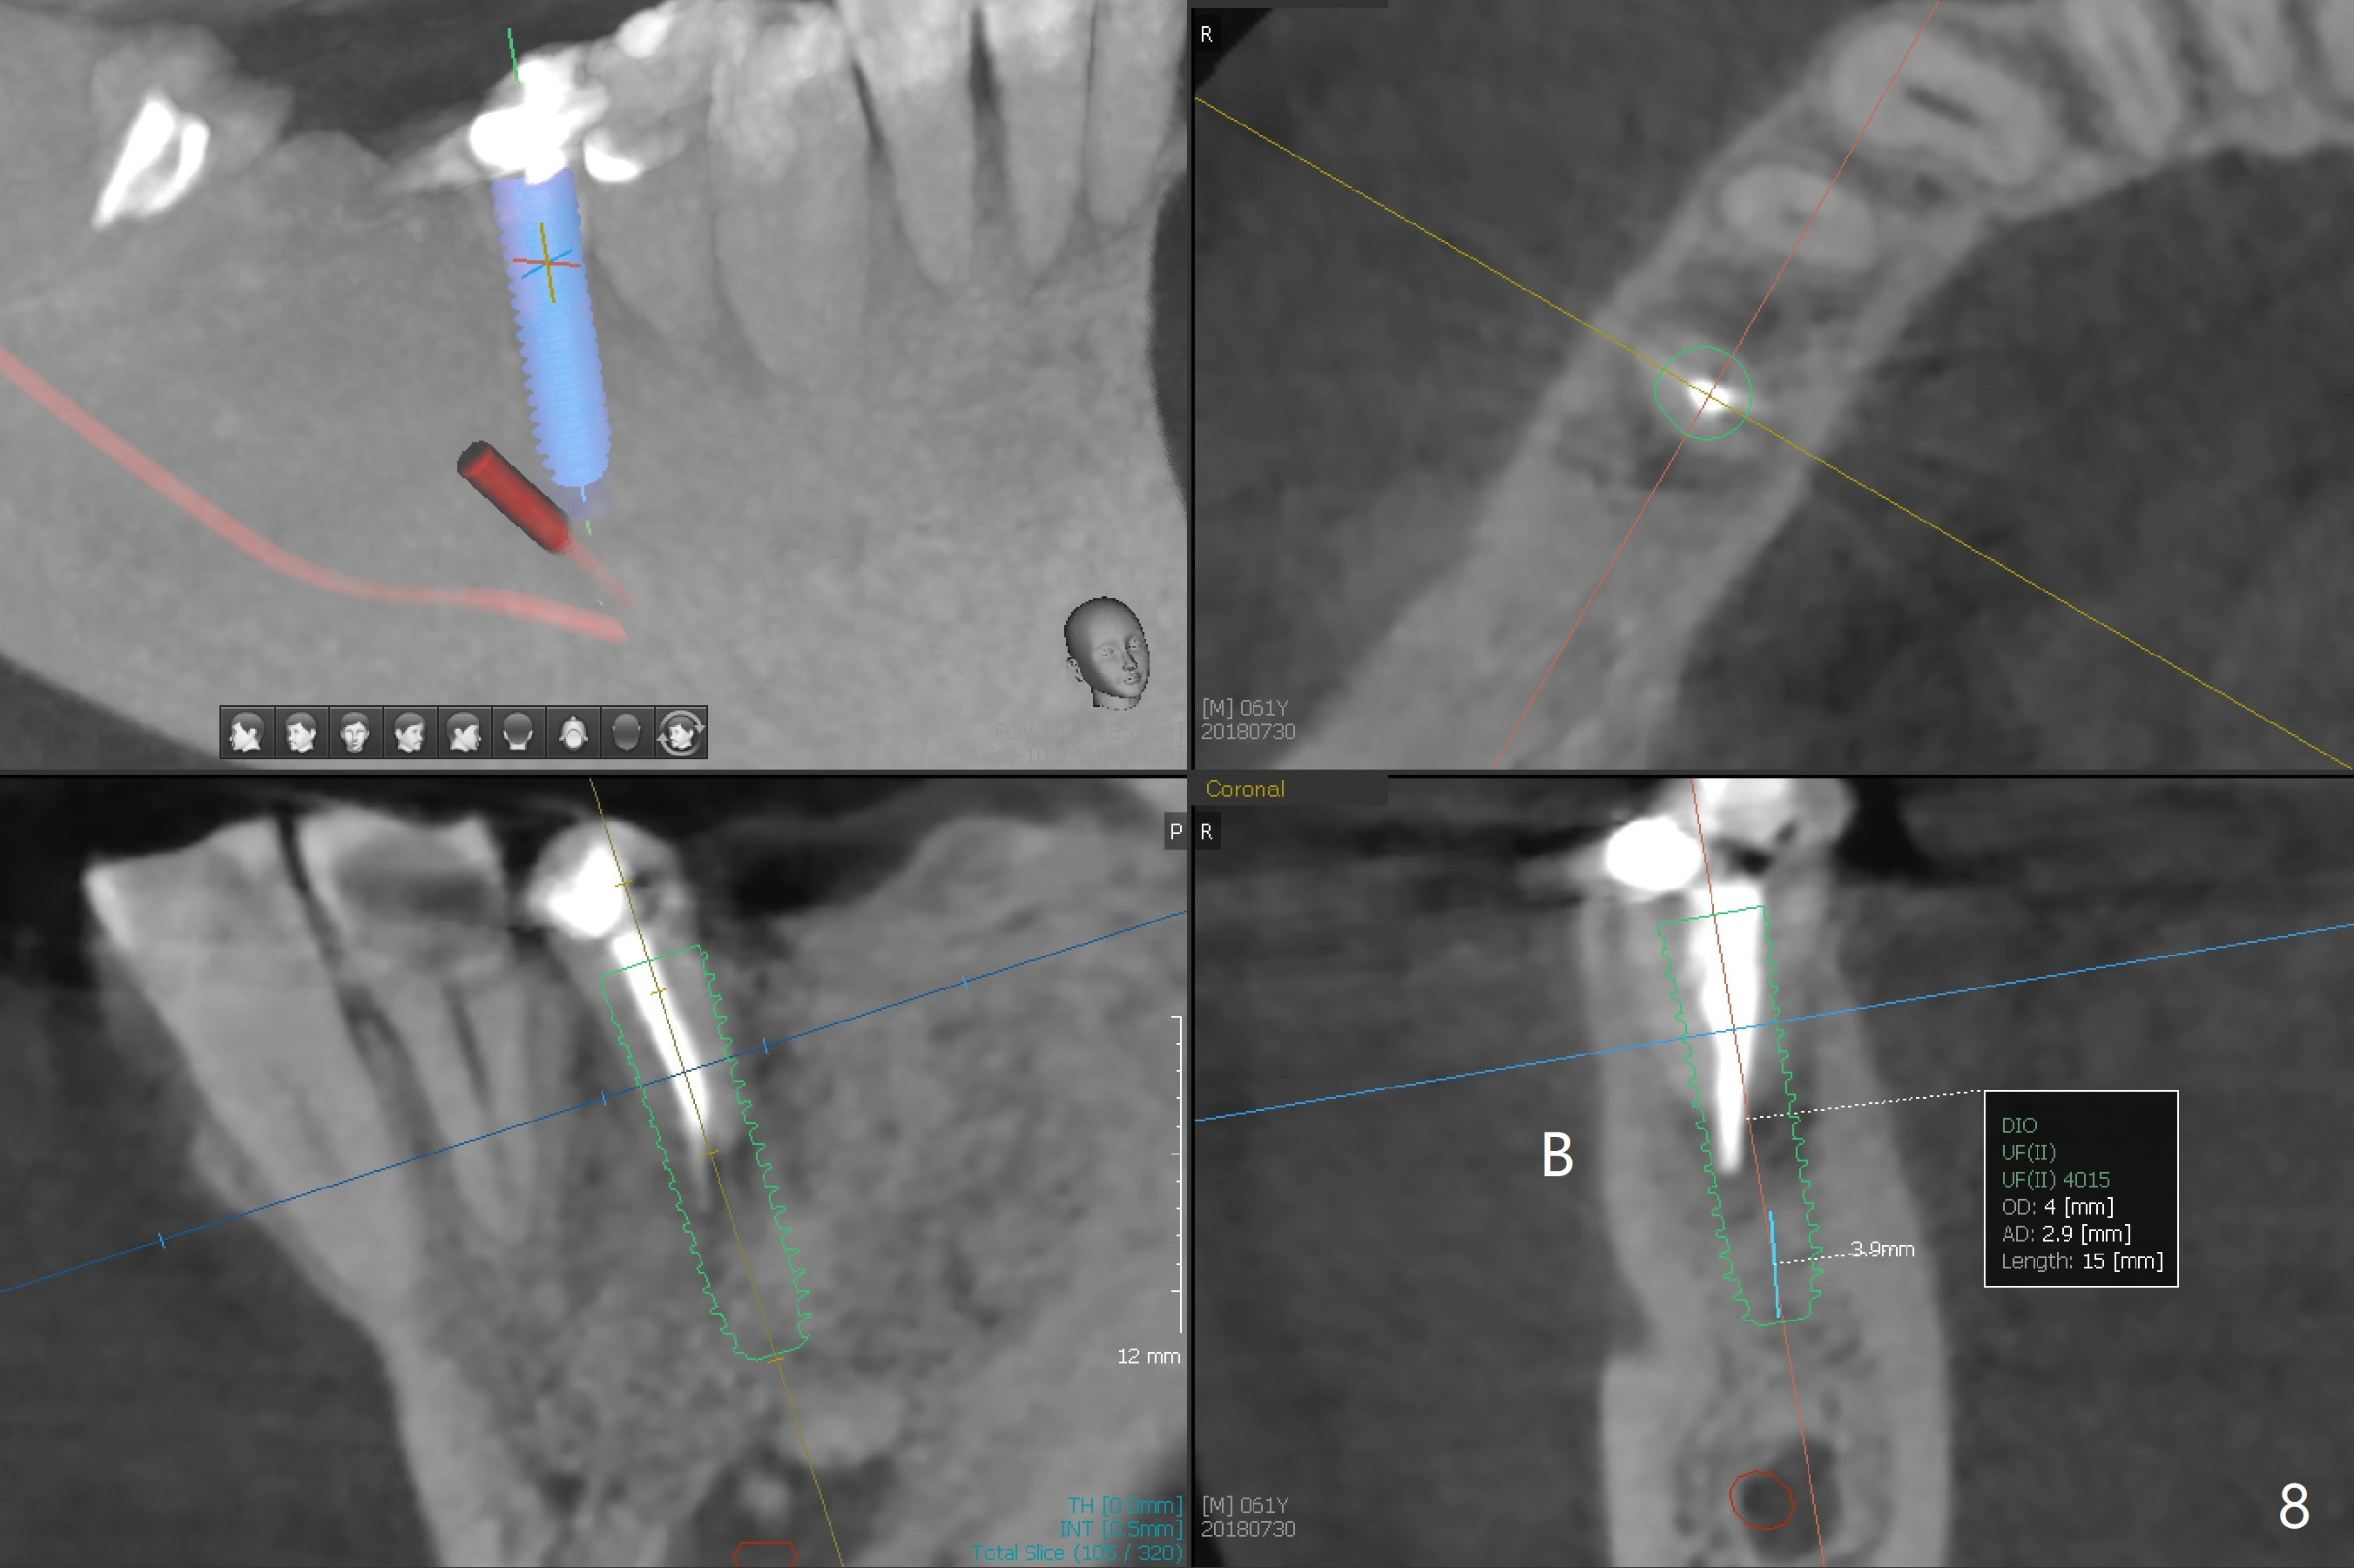

An endodontist refuses RCT retreatment at #29 because of short root. The patient is hesitant about apicoectomy. After discussion of advantages and disadvantages of the latter vs. extraction and implant, the patient chooses the extraction. The latter turns out to be smooth with socket preservation (Fig.4, 5 *). Immediately postop PA shows bone loss at #30 and minor degree around the apex of #31 implant (Fig.4 <), which is probably related with hard bone and bone necrosis due to heat. The headache disappears 1 week postop (Fig.6). The patient does not take pain medication. There is no percussion at #30 (Fig.7). The healing abutments are stable. The patient will return for #30 and 31 restoration nearly 4 months postop and 2 months post #29 extraction. Splinted provisional will be placed if the implants heal. Impression will be taken for #29 guide 4 months post socket preservation. After re-analysis of CT, it appears that a long implant (4x15 mm to gain 3.9 mm fixation in the native bone) will be placed free hand at #29 four months post socket preservation (Fig.8). The bone loss around the implants at #30 and 31 persists 3.5 month postop, while the socket heals at #29 2 months post socket preservation (Fig.9). When the healing abutments with plaque are removed, there is granulation tissue around the gingival cuffs with tenderness. The abutments with heavy plaque (similar to that in Fig.7) are reloaded after cleaning with OHI. The patient returns for CT and impression for #29 guide 3.5 months post socket preservation and 5 months post implant placement. While bone necrosis remains severe at #30, the socket at #29 seems to have healed (Fig.10). Oral hygiene improves with healthy gingiva, but there is tenderness when a cementation abutment is placed. Implant design before and after extraction at #29 (Fig.11,12). Gingiva becomes inflamed at #31 when a splinted provisional is being worn to intrude the opposing supraerupted teeth; bone resorption remains severe in the previous distal socket and the mesial necrotic area (Fig.13 S, N). Pain persists after placement of a healing screw. In spite of severe bone loss, especially distal, the buccal plate is present. When the implant at #31 is removed, there is a large defect with granulation tissue apicobuccal to the buccal plate, corresponding to the presumptive mesial necrotic area (Fig.13,14 N). Vanilla graft mixed with PRF ("sticky bone" too rigid) is placed in the defect, followed by a piece of PRF membrane and 6-month one. The pain appears not to reduce and nearly 1 month later transfers to the buccal of #30.